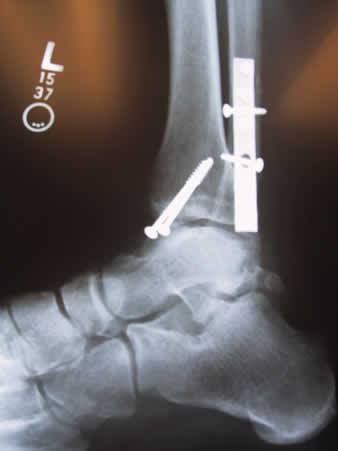

Anyway, the end result looked like this: